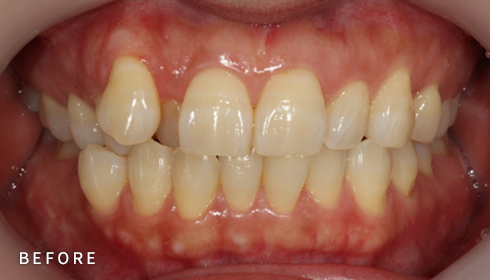

PROGRAM 03

돌출입 교정

입이 나와보이는 인상, 교정으로 부드럽게

입이 들어가도 앞니 각도 조절에 실패하면 옥니나 합죽이가 되어

심미성과 기능 모두 만족하기 어렵습니다.

개인별 분석을 통해 적절한 발치를 결정하고, 앞니를 자연스럽게 뒤로 배치해

안모 균형과 자신감을 되찾는 정밀한 돌출입 교정을 진행합니다.